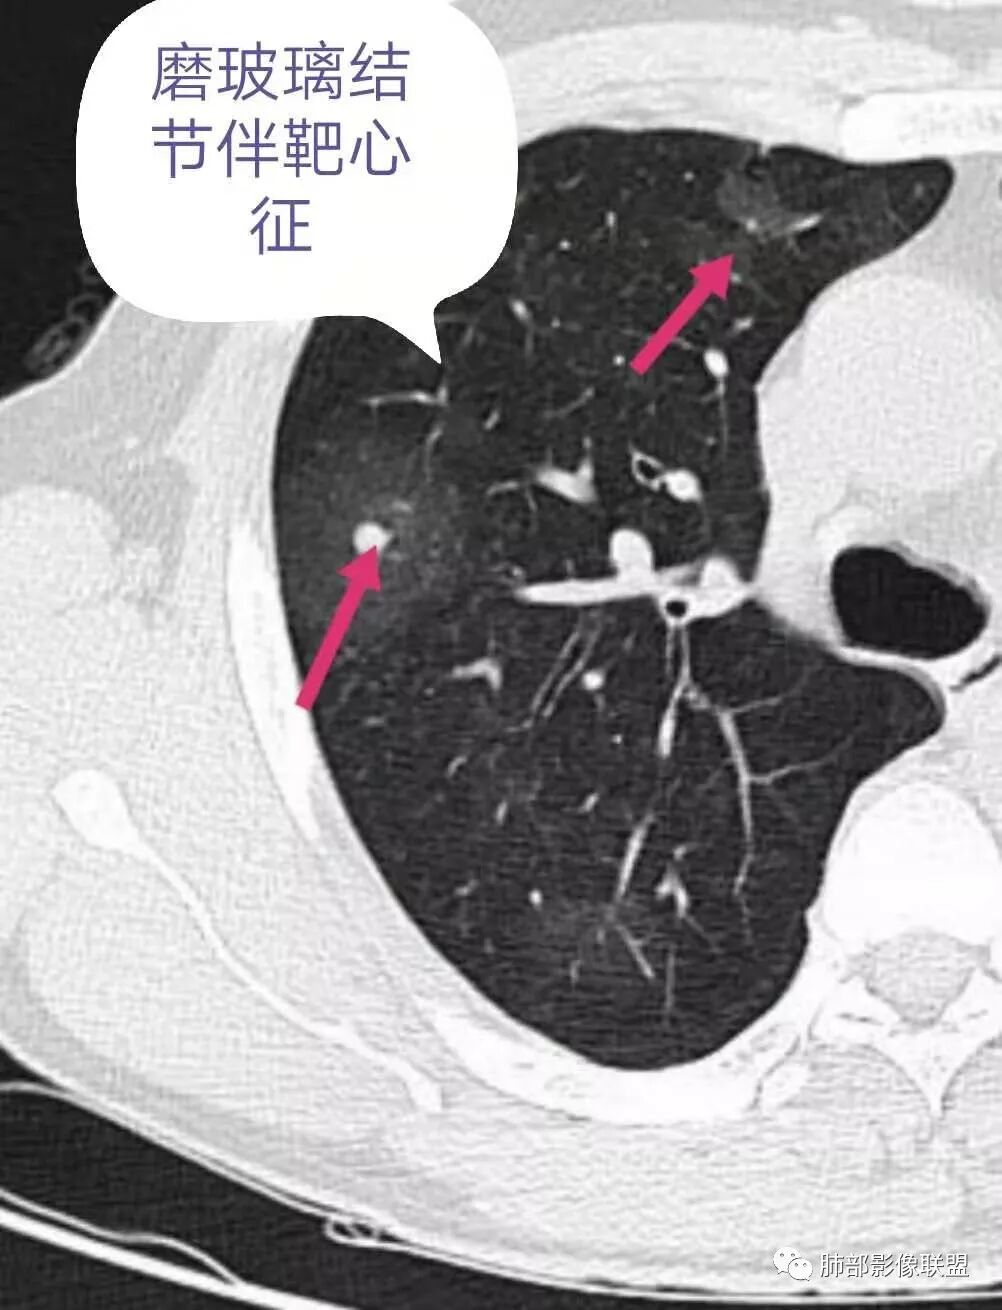

1.双肺多发磨玻璃结节影,边界可分辨,病灶中央都可见一实性密度小结节影,注意不是钙化。这些病灶形态及密度是如此相似,宛如身着厚厚一层晕影蜉蝣深海之中,称之为“点晕征”。

注意:多发、点、厚晕

2.肺部“点晕征”病灶更多见于血管肉瘤、上皮样血管内皮细胞瘤、肺动脉肉瘤等等。

双肺多发磨玻璃影,大部分中央可见增粗血管影,部分血管边缘模糊破坏,左侧肩胛骨骨质破坏,周围巨大软组织肿块,软组织肿块内可见坏死及肿瘤骨,考虑肩胛骨骨肉瘤并双肺多发转移(点晕征)。

47岁男性,咳血痰左肩背痛1月余,左肩胛骨破坏,破坏处及周边见软组织肿块,左肩胛区包块并皮肤破损,破损处无渗液、无脓不支持结核。两肺见多发磨玻璃影,沿血管走行,其内血管明显增粗,部分磨玻璃影内可见点状实性结节,呈点晕征,各磨玻璃影形态密度基本一致,提示同一来源,支气管未见明显增厚扩张——不支持气道来源。小叶间隔无增厚及纵隔未见明显肿大淋巴结——感觉淋巴瘤可能性较小。胸腹部皮肤散在红斑。整体考虑左肩胛骨恶性肿瘤并两肺转移。

影像特征:左肩胛骨区巨大软组织肿块,可见肩胛骨骨质吸收破坏,肺内多发随机分布结节,和血管关系密切,周围模糊GGO影,结合病史,左肩肿块考虑原发肿瘤,肺内考虑血行性转移伴出血;